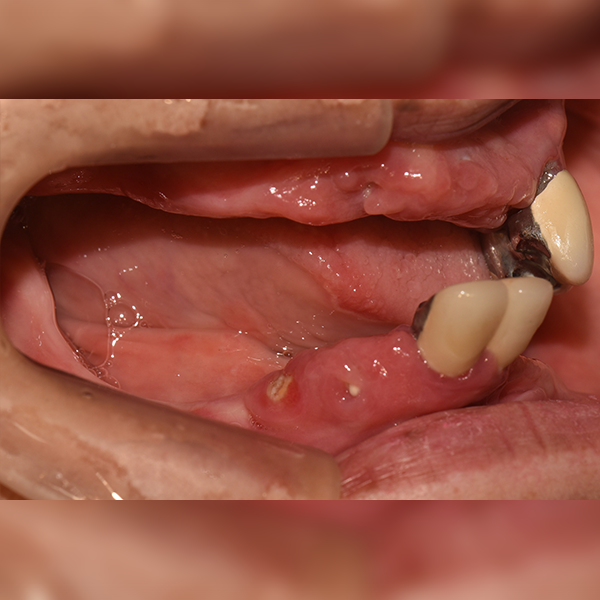

3. Trường hợp 18. Cô/Chú Park*Soon, 60 tuổi 2019-12-09 / 2020-11-05

Toàn hàm/Toàn bộ / Ghép xương | Tiền mê

Trường hợp 18. Cô/Chú Park*Soon, 60 tuổi 2019-12-09 / 2020-11-05